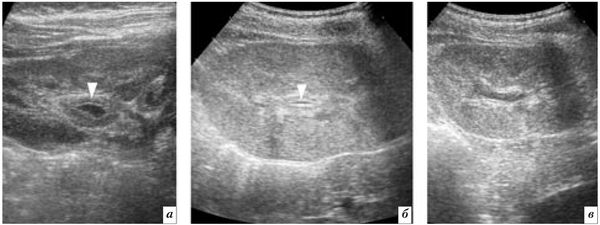

Диагностировать пиелит можно только после проведения компьютерной томографии (КТ) с внутривенным контрастированием, т. е. с введением специального вещества (обычно йодсодержащего) для улучшения видимости органов и тканей. Однако при выполнении этой процедуры организм получает определённую дозу облучения, поэтому предварительно пациенту делают ультразвуковое исследование (УЗИ). С его помощью можно увидеть размер почки, пузырьки воздуха и нарушение оттока мочи. Если УЗИ подтверждают подозрения врача о наличии пиелита, пациента направляют на КТ.

![Как выглядит пиелит на УЗИ [8] Как выглядит пиелит на УЗИ [8]](/media/bolezny/pielit/kak-vyglyadit-pielit-na-uzi-8_s.jpeg?dummy=1754648729305)

Как выглядит пиелит на УЗИ [8]

Компьютерная томография позволяет детально рассмотреть паренхиму почки, обнаружить различные осложнения (например, нагноения или воздух в окружающей клетчатке), а также чётко визуализировать окружающие ткани. Однако КТ с внутривенным контрастированием имеет некоторые противопоказания: если у пациента есть аллергическая реакция на йод-содержащие препараты или уровень креатинина в его крови превышает 150 мкмоль/л, проведение такой процедуры считается опасной для здоровья, поэтому перед исследованием необходимо проконсультироваться с врачом.